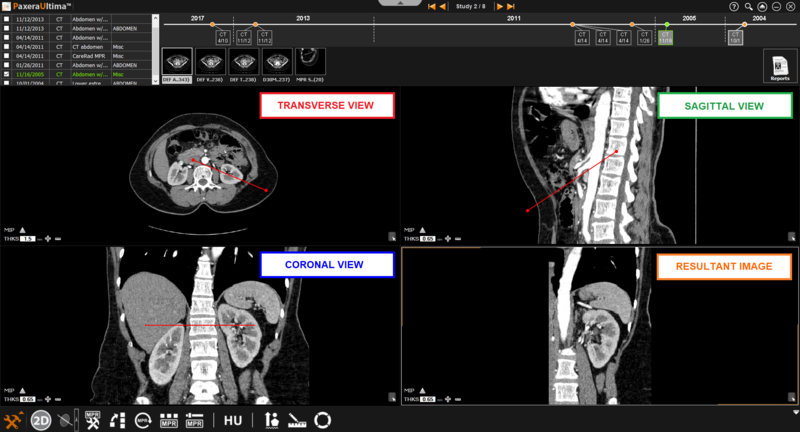

9.4.4. Oblique Mode

The oblique mode is similar to the bioblique mode as the user can adjust the angle of the plane. However, you can only manipulate one plane at a time.